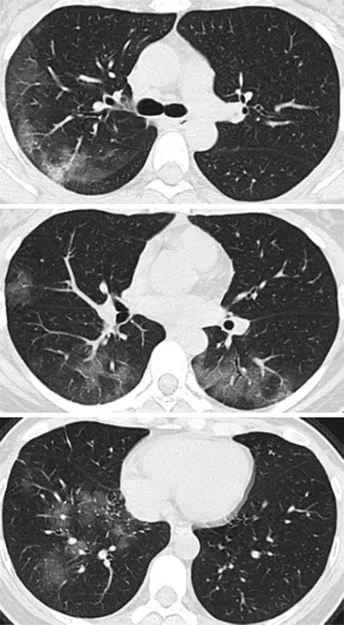

01-2.webp

图片来自《Radiology》杂志

病例2,41岁女性,去了一趟武汉,

回来后,开始发热咳嗽,

4天后,她感觉呼吸困难,

去医院X线胸部拍片,检验血液,

都没有发现有啥异常。

但是CT扫描发现

两侧肺周边出现多处斑片状毛玻璃样显影。